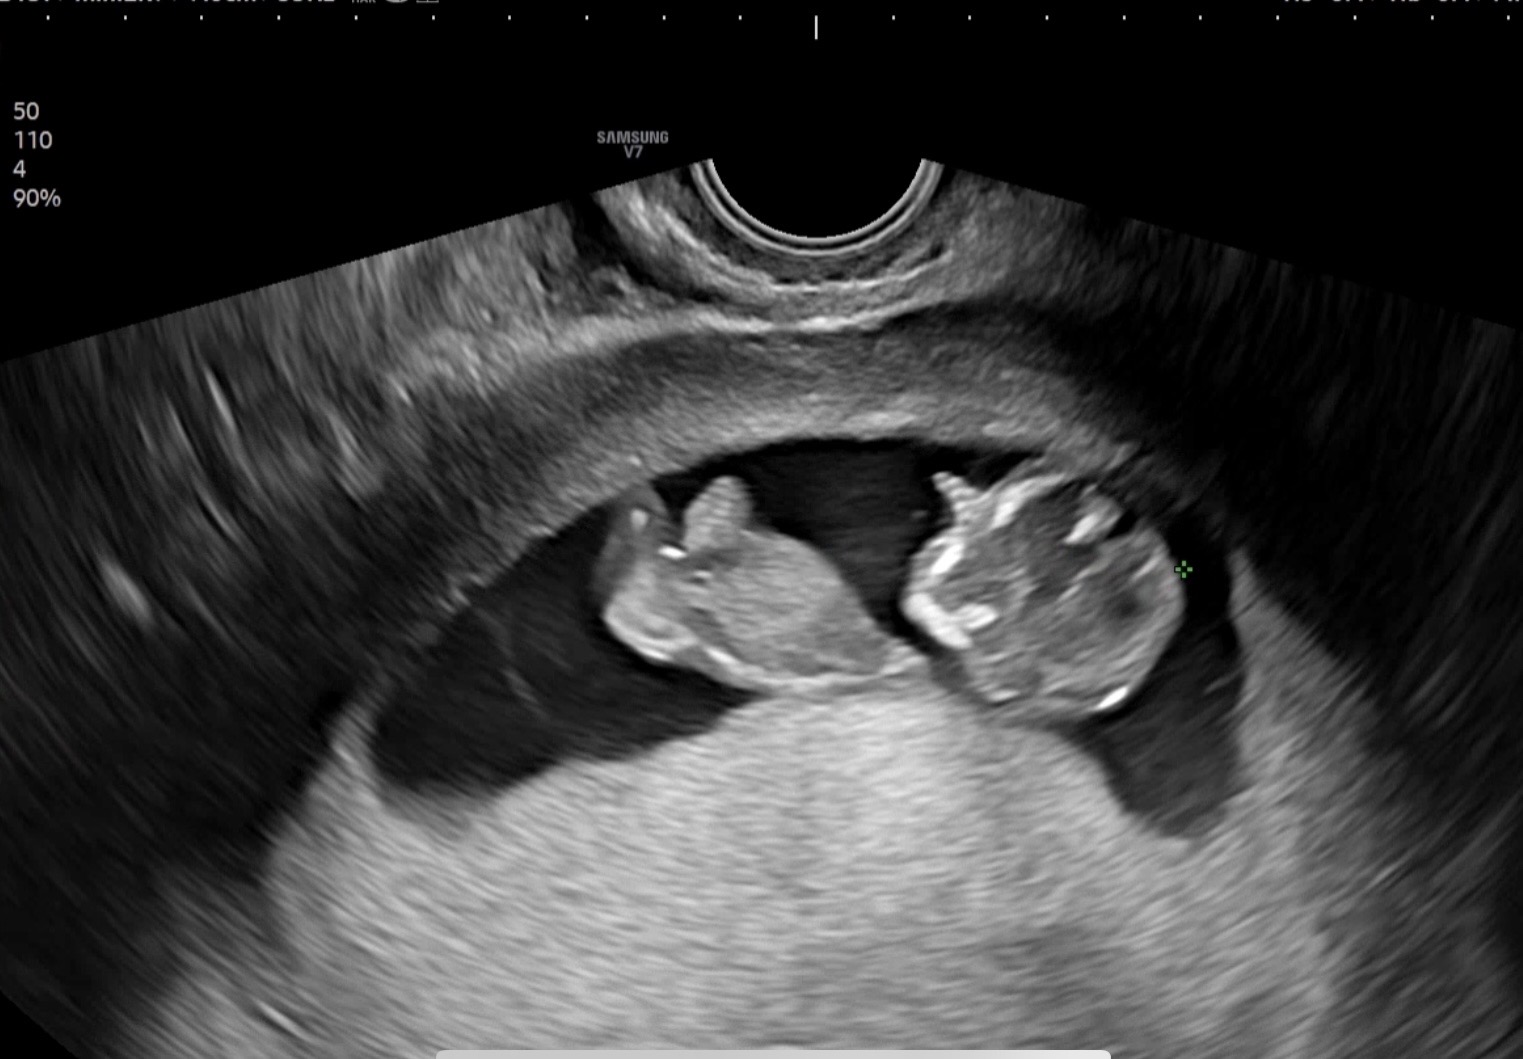

임신 7~8주쯤 혈압이 높아 혈압약을 복용하기 시작하고 9주쯤 요당발견하고 임당이네요ㅠㅠ 낼모레 재검입니당,, 임신초기에 알게되서 매주 심장내과, 내분비내과, 산부인과 다니며 매일 혈압기, 혈당기 달고 살고 식단도하니 우울극치인데 어제 아가보고 힘이나여..! 10주차인데 발도 뻥뻥차며 놀고 벌써 손가락 발가락이 다 생겨서 이마로 가져가는데 꼭 자기는 건강히 잘크고있다고 충성! 해주는거같아요..ㅋㅋㅋㅋㅋ 혈압, 혈당 있으신 엄마들 화이팅이에요!!!!